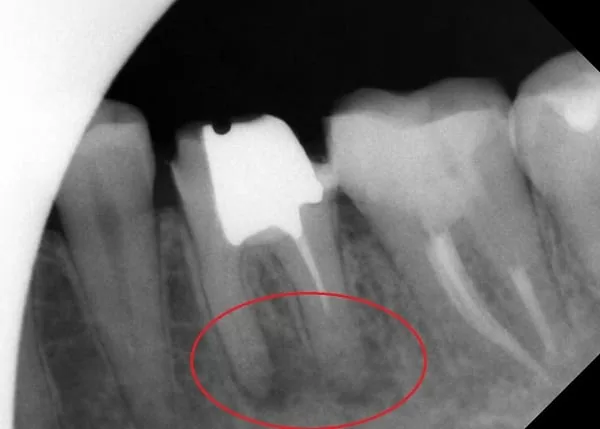

2. 開始治療後,發現此牙有三個神經管,且其中一個根管呈現較難治療的彎曲C狀,經過顯微鏡輔助根管治療後,三個根管皆已清潔乾淨並達到理想的工作長度與寬度。(如下圖)

3. 接著進行第一大臼齒的治療;首先,先移除原本的假牙冠,並透由X光片檢查牙根尖發炎狀況,發現近心和遠心牙根尖皆受到感染而呈現慢性發炎。

4. 因患者根管鈣化嚴重無法正確定位路徑,需配合超音波將鈣化物質震盪移除,並不斷沖洗根管死角,清潔發炎根管,以便正確定位根管路徑,並將鈣化根管通至根尖。

5.最後,醫師搭配使用法國的Lokki Nd:YAP牙科專用雷射輔助治療,將根管有效高溫殺菌,並配合顯微鏡將根管空間緻密地封填起來,並完成左下第一大臼齒的根管治療。

下圖中可發現,根尖發炎擴散至齒槽骨的狀況,在兩個禮拜內就已獲得有效控制且有改善。